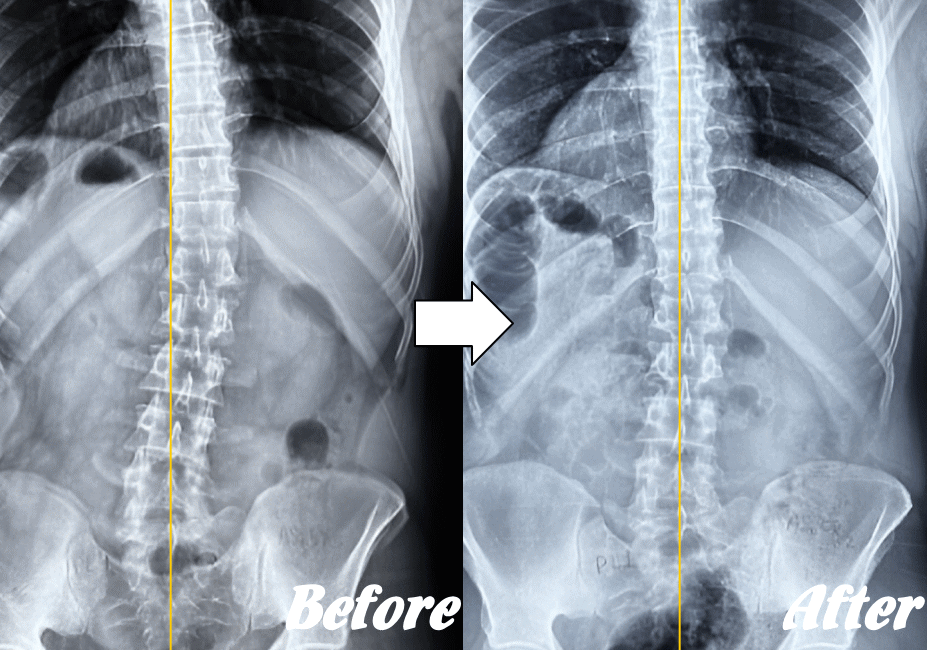

【体の整体】による変化

※ X線/MRI/CT検査画像のデータをお持ちの方はご持参いただければ当院で参考にさせていただきます。

施術前と施術後01